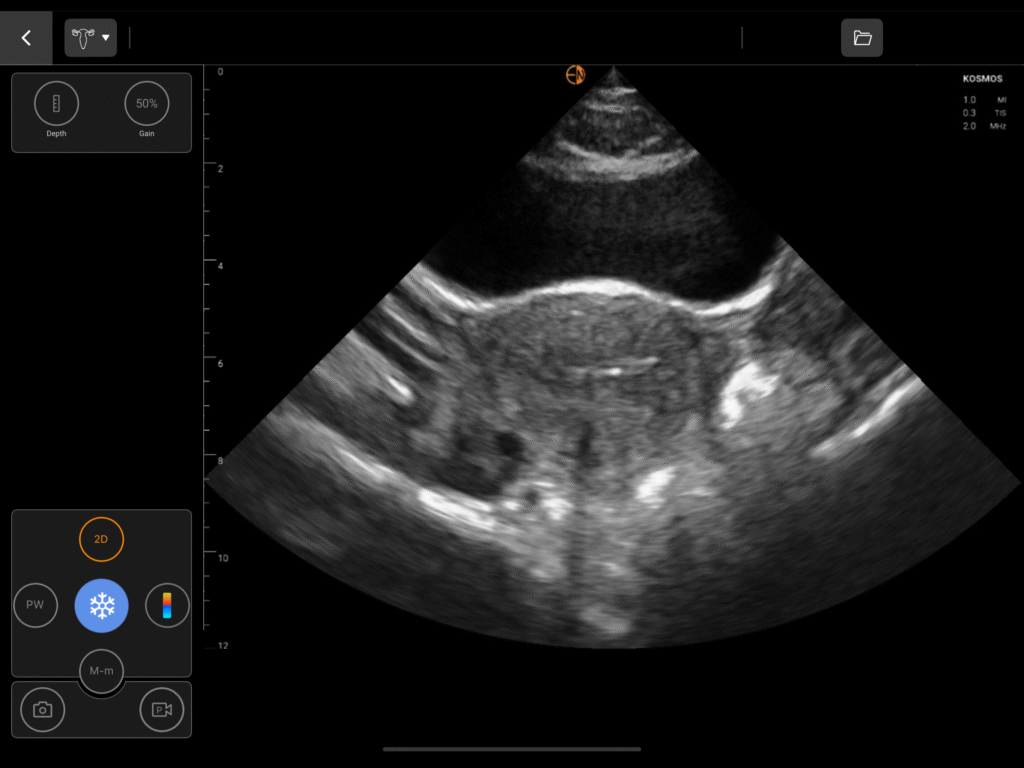

OB/GYN Image Gallery

Dedicated measurements for the uterus, endometrium, ovaries, including volume calculations for cysts and masses, and bladder.

Assess fetal head position, station, and presentation (cephalic/breech) to guide labor management.